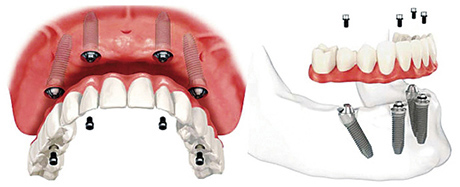

而像孟女士这样半口、全口的缺牙者,采取的是All-on-4即刻负重,半口缺牙只需在牙槽骨植入4颗植体,在当天戴上整排牙齿,恢复咀嚼力。将原本长达半年到1年的修复时期缩短到1天。不仅在戴牙当天可以吃饭,随着时间的推移,患者感到牙齿越来越有力。

而像All-on-4这样特殊的半口、全口种植牙,在种植体的基台上安装“拱形连桥”牙冠,这样整个种植牙的受力就呈现出“拱形”的特征,即一点受力会均匀地分布到整体,这在建筑学上是最为稳固的形状。这种稳固的结构也使在植入种植体的当天,就可以安装牙冠恢复美观和咀嚼。